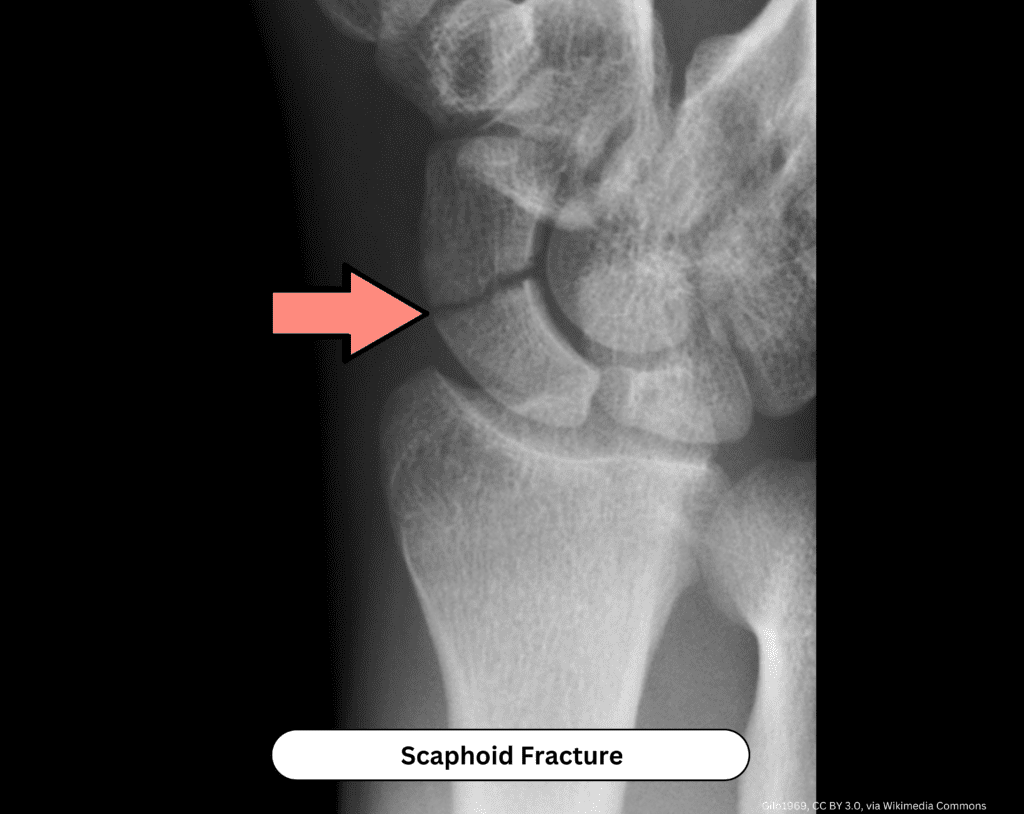

Scaphoid Fracture

Scaphoid fractures are one of the most important wrist injuries to recognize early.

The typical mechanism is a fall on an outstretched hand (FOOSH). Patients usually present with wrist pain, with or without swelling, and initial X-rays may be normal.

The key exam finding is tenderness in the anatomic snuffbox.

Because of the scaphoid’s blood supply, missed fractures can lead to nonunion or avascular necrosis.

If clinical suspicion is high despite normal imaging, the safest approach is immobilization in a thumb spica splint with repeat or advanced imaging. The patient should follow up with orthopedics in 7–10 days.

Important point: When the mechanism and exam suggest a scaphoid injury, treat it as a fracture until proven otherwise.